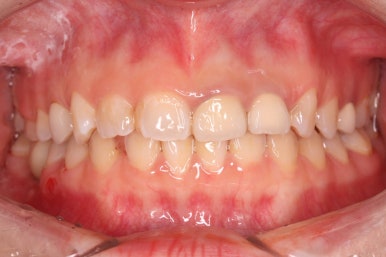

부산부분교정 키다리아저씨치과에 처음 내원하셨을 때의 얼굴 모습입니다.

치아가 약간 삐뚤어져 있는 모습을 보이긴 하지만 환자분 스스로 개선을 할 필요성을 느끼지 못하셨고 적극적으로 개선을 해야 할 만큼의 얼굴 모습이 아니기에 어금니만 하기로 한 것이죠.

교정을 하고 나서도 얼굴모습, 정면에서 바라본 치아의 모습이 변화가 전혀 없이 현재 상태를 유지하게 됩니다.

부산부분교정을 하기 전과 후의 모습입니다.

부분교정으로 하였기 때문에 다른 치아의 변화는 전혀 없습니다. 또한 비교적 짧은 기간으로 원하는 목표를 달성했죠.

부분교정으로 매우 만족스러운 결과를 이끌어 냈습니다.